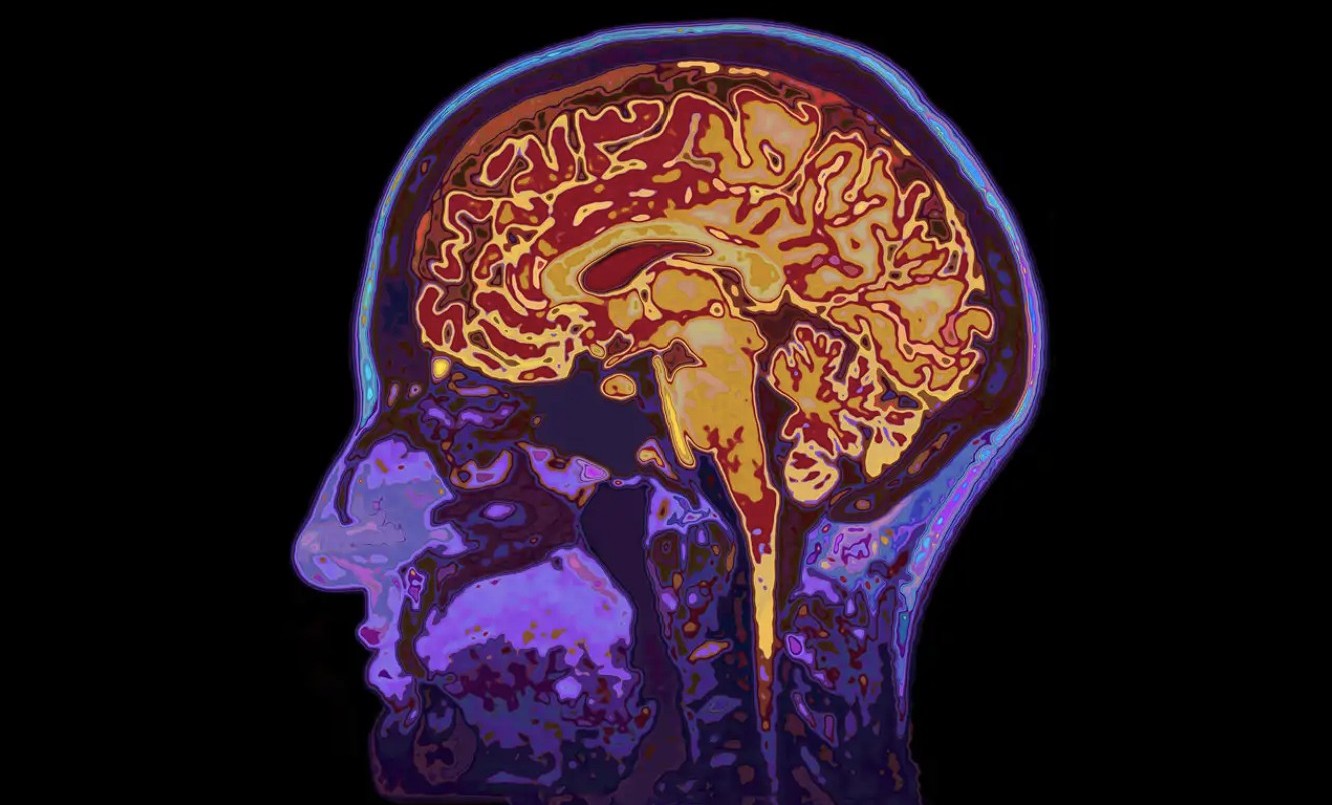

Cómo mantener el cerebro joven: hábitos clave avalados por la ciencia médica

Ejercicio, descanso, aprendizaje y vínculos sociales: qué dice la neurociencia sobre el cuidado del cerebro a lo largo del tiempo.

El paso del tiempo impacta en todo el organismo, y el cerebro no es la excepción. Sin embargo, la ciencia médica sostiene que existen conductas concretas que ayudan a mantener la mente activa, flexible y saludable, incluso en la adultez y la vejez. Lejos de mitos o promesas infundadas, la neurociencia respalda una serie de hábitos que favorecen el buen funcionamiento cerebral.